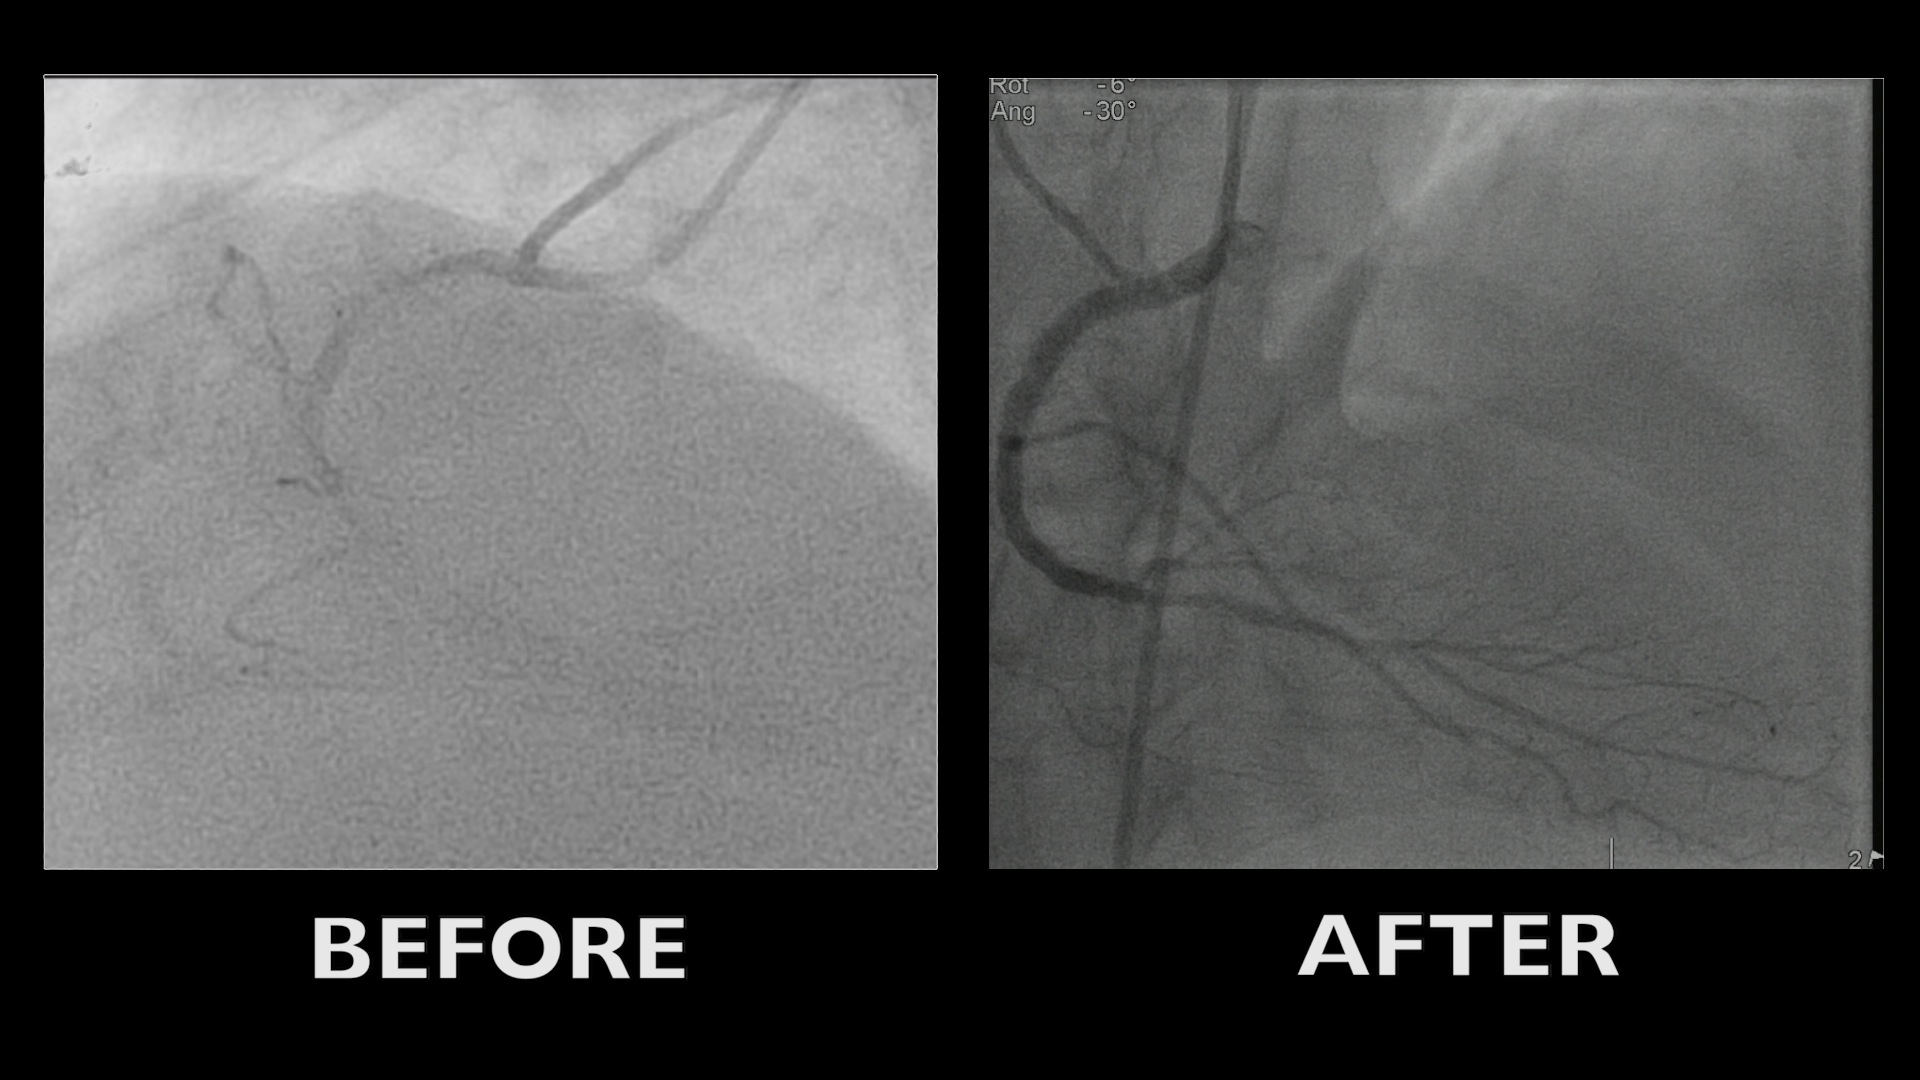

IMAC 2019 : Fenestrated EVAR for chronic dissection thoracoabdominal aortic aneurysm

Case of the month: October 2021